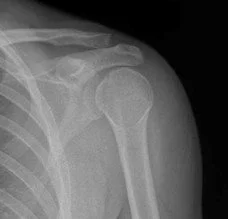

2. Obtain X-rays to confirm fracture

Basic Principles of Fracture Reduction:

1. Longitudinal traction-countertraction

2. Recreate and exaggerate mechanism of injury while holding traction-countertraction

3. Alignment of the fractured ends while holding traction-countertraction. Then release traction to stabilize.

4. Post-reduction XR to verify alignment

4. Immobilization via Splinting/Casting

6. Reestablish neurovascular status